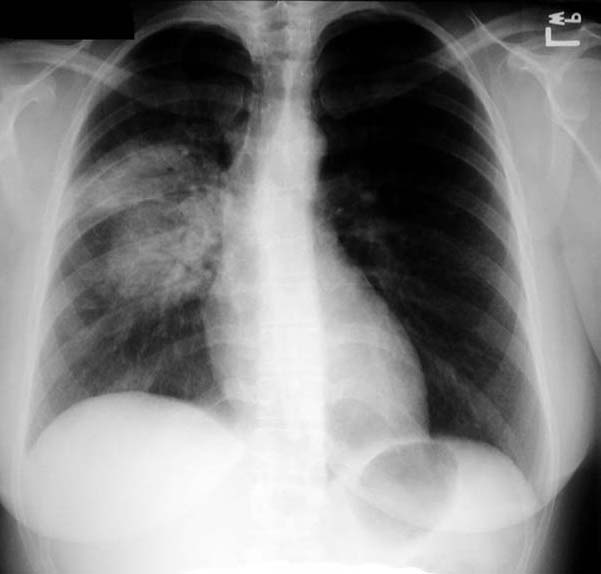

Blastomycosis

• Round pneumonia

• "Mass" like density with air bronchogram